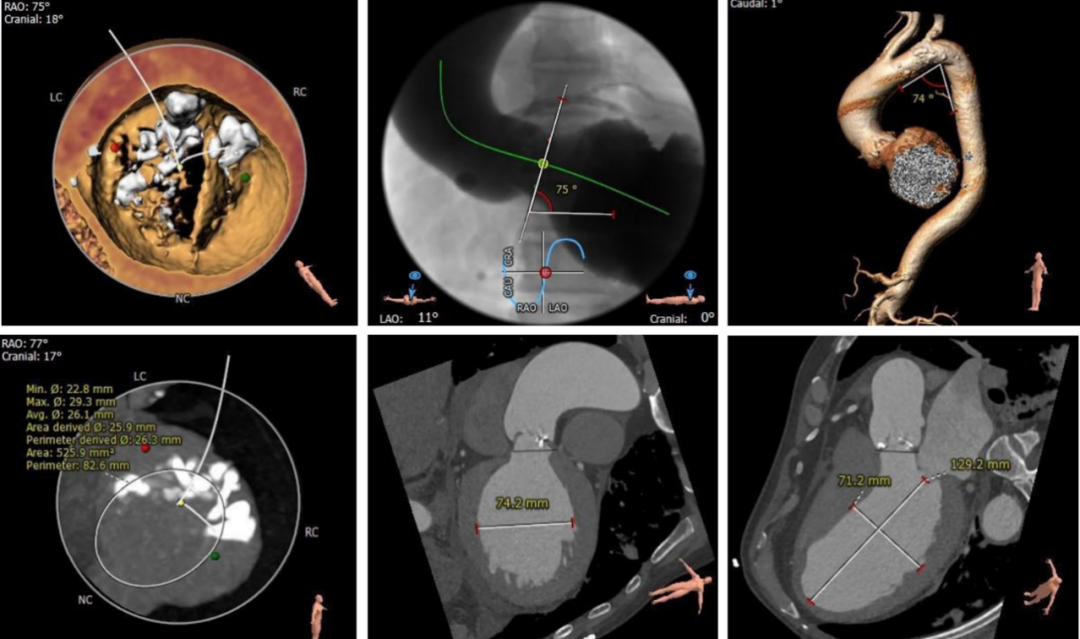

CT显示Type0型二叶瓣,瓣叶中重度钙化伴增厚粘连,存在人工瓣膜形变、瓣环撕裂及根部损伤风险;大瓣环、钙化分布不均匀及瓣口形态限制,人工瓣膜锚定难度较高,瓣周漏风险高,存在瓣中瓣风险。严重横位心(75°),输送系统过弓、跨瓣难度较高。

对于此例病人,严重横位心75°,器械需要出色的柔顺性与通过性在手术过程不损伤血管;瓣膜需要良好的径向支撑力,避免出现下滑的风险。在武汉大学中南医院心脏中心结构性心脏病团队通力协作下,顺利完成此例高难度手术,术中评估TaurusElite AV29mm瓣膜锚定良好,术后造影结果显示瓣膜形态、位置良好,仅少量瓣周漏。手术即刻超声测量,主动脉瓣工作良好,瓣口流速从术前的5.2m/s改善为1.8m/s,跨瓣压差从术前的106mmHg改善为8mmHg。

其次,术中投照角度选择。合适的投照度能够帮助临床将3维结构2维化,获得更好的观察角度。二叶瓣患者TAVR术中需要选择双窦展开的体位,这个角度下边能够更好的在DSA上看到两个窦的展开情况以及瓣膜的贴合情况。对于反流的患者,我们更加关注植入过程深度的变化,故采用Cusp Overlapping技术。手术过程中为保障瓣膜精准的定位,术中我们会先释放到输送器胶囊与瓣架底端齐平的位置再造影判断其与窦底位置,进而慢慢释放让瓣膜与组织贴靠,提供锚定力后再快速释放到工作位,进而多体位造影+超声评估,如果不合适再回收进一步调整。